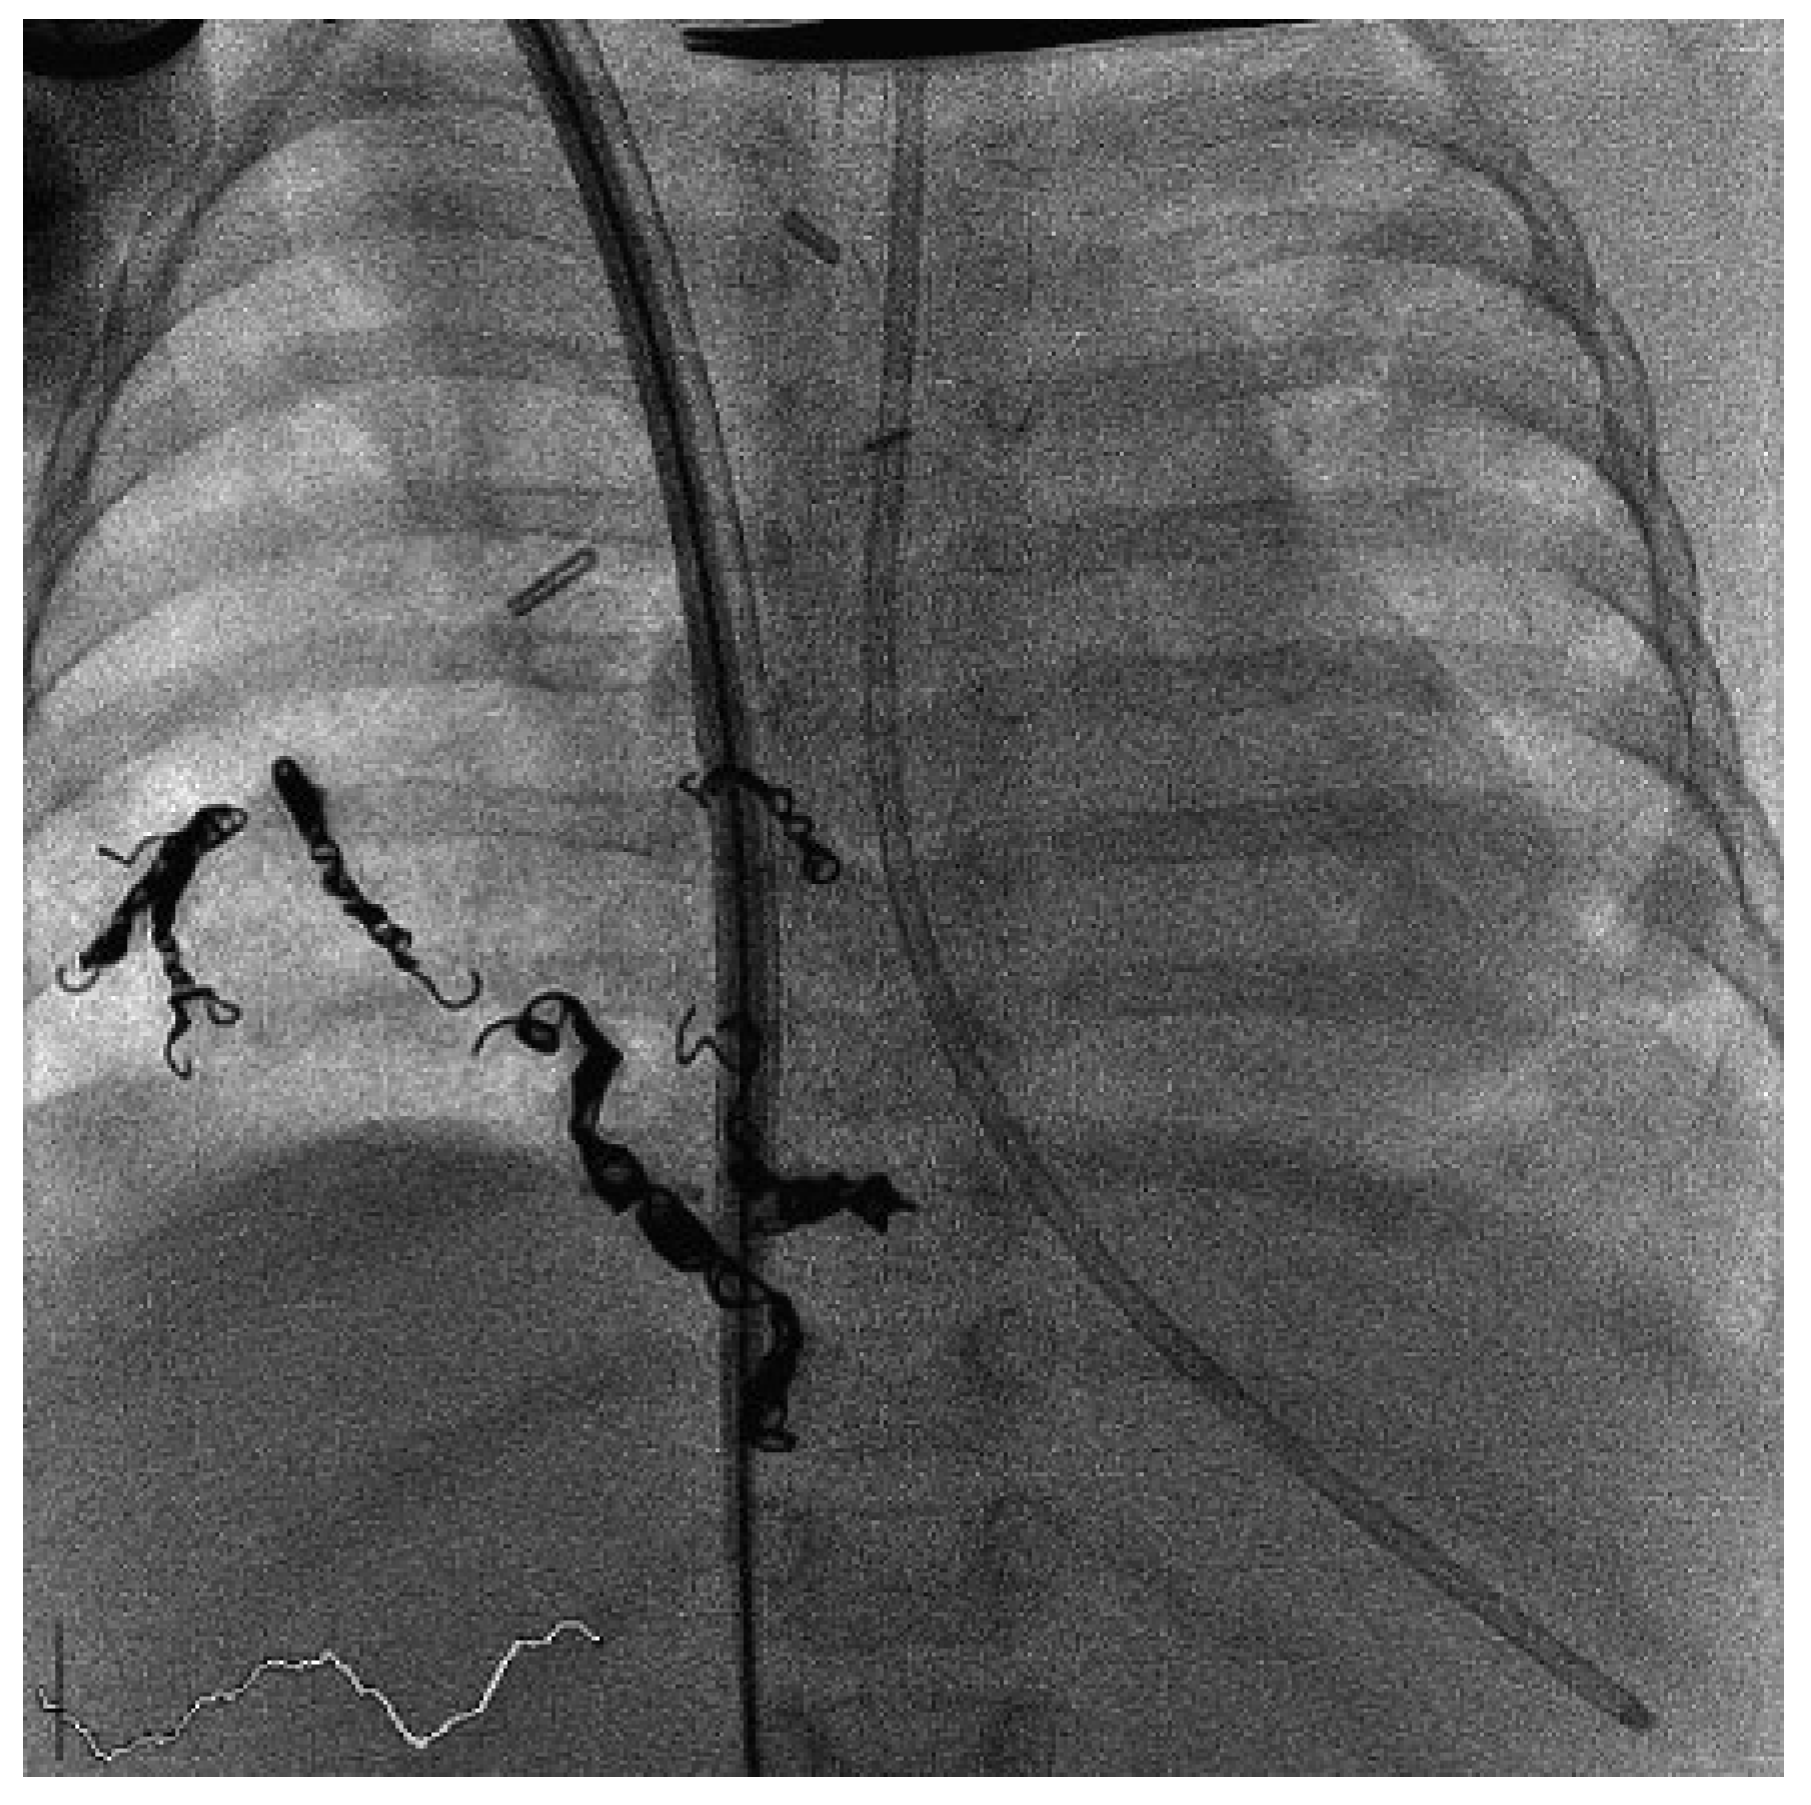

During ECMO implantation, echocardiography can guide the insertion and correct placement of the cannulas and document the volume state of the left ventricle. If VV-ECMO with a dual-lumen cannula (AVALON®, Avalon Laboratories, LLC, California, USA) is inserted via a single site (internal jugular vein), we use echocardiographic or x-ray guidance in the cardiac catheter laboratory to ensure adequate orientation of the ports of the cannula (Figure 2). Their proper position must be confirmed with echocardiography, especially the location of the outflow lumen, which must be positioned in the centre of the right atrium with flow directed towards the tricuspid valve. The hepatic veins and the distal inferior vena cava should not be congested.

Figure 2. Implanted VV-ECMO using a single-lumen cannula (AVALON) showing proper placement in the catheter laboratory.